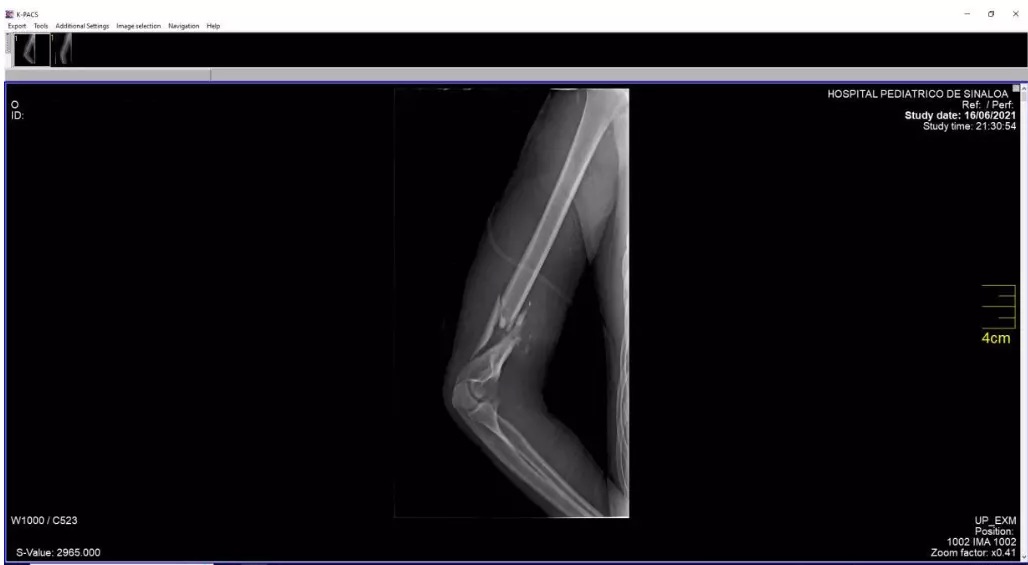

Cuando se relatan las cifras también se revelan las problemáticas sociales, como lo explica la psicoterapeuta Ángeles Vizcarra Rojas, adscrita al Hospital Pediátrico de Sinaloa.

El Doctor Martín Borboa, profesor de Medicina Legal de la Universidad del Policía, explicó que dicha fragilidad puede ser un factor positivo, pues la atención médica sobre el físico de una persona adulta es aún más difícil en comparación con una niña o un niño.

“No es lo mismo el cuerpo de una persona que ya se terminó de formar que el de un niño. Pero esa fragilidad también es un peligro, porque eso puede provocar que sus heridas sean más sencillas de hacerse con muy poco esfuerzo”, aseguró el ex director de Medicina Forense en Servicios Periciales de la Fiscalía General de Sinaloa.